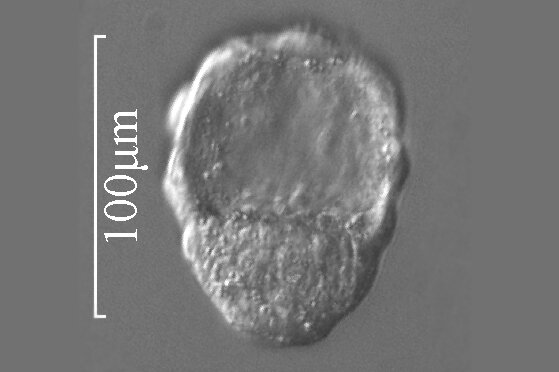

Bruzdkowanie jest pierwszym etapem życia zarodkowego. Rozpoczyna się pierwszym podziałem zygoty, około 30 do 36 godzin po zapłodnieniu. Komórki powstałe po podziale zygoty nazywane są blastomerami. Zarodek zbudowany z 12‑16 blastomerów ma formę grudki i nazywany jest moruląmorulą. W dalszym etapie blastomery rozsuwają się, a zarodek przyjmuje formę pęcherzyka, z jamą w środku. Jest to blastocysta, która przesuwa się przez jajowód i dociera do macicy, gdzie ok. 6. lub 7. dnia od zapłodnienia następuje implantacja zarodka w błonie śluzowej macicy.

I trymestr | 30‑36 godz. | 0,15 mm | Zapłodniona komórka w jajowodzie ulega podziałowi. ![]() Źródło: Englishsquare.pl Sp. z o. o., licencja: CC BY-SA 3.0. |

3–4 dzień | 0,15–0,2 mm | Kolejne mitotyczne podziały zygoty, jej wędrówka przez jajowód. Zygota w stadium 4 blastomerów: ![]() Źródło: Englishsquare.pl Sp. z o. o., licencja: CC BY-SA 3.0. Zygota w stadium 8 blastomerów: ![]() Źródło: Englishsquare.pl Sp. z o. o., licencja: CC BY-SA 3.0. Zygota w stadium moruli: ![]() Źródło: Englishsquare.pl Sp. z o. o., licencja: CC BY-SA 3.0. | |